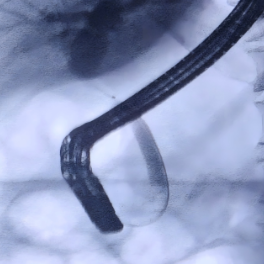

专家团队达成共识:病变部位不能排除为恶性肿瘤所致,应立即为患者实施胆道子镜检查+组织活检,明确病变性质后再制定个体化治疗方案,如果为良性病变,内镜治疗即可。通过子镜观察到患者胆总管上段存在一处长约1cm的狭窄并增厚胆管壁,并在病变部位精准钳取3块组织样本。果然,病理报告提示腺癌,这一结果证实了专家团队的初步判断。拿到诊断报告后,患者及家属陷入了悲痛之中,但罗宏武主任团队及时给予了心理疏导与信心鼓励,专家们的专业解读与暖心安慰,让患者及家属重新燃起了希望。

据中南大学湘雅三医院相关负责人介绍,医院肝胆胰外科一病区致力于肝胆胰系统疾病的临床诊疗工作,在微创外科治疗、内镜技术应用及肝硬化门静脉高压症的规范化综合治疗方面形成了显著特色。该团队常规开展胆道子镜检查、经内镜逆行胰胆管造影术(ERCP)、超声内镜(EUS)等复杂操作,在国内内镜诊疗领域处于领先地位,为胆管狭窄、胆道结石及胆胰肿瘤等疾病患者提供精准诊断与治疗。